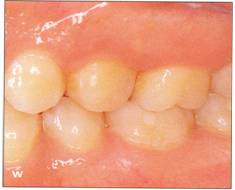

Fi 545e45f g S.8a Preoperative panoramic view. The maxillary left first premolar will be extracted for orthodontic reasons and transplanted to the area of mandibular left second premolar in a 15year-old female. Fi 545e45f gs S-8b to 5-89 Preoperative intraoral view. Fi 545e45f g S-8h Preoperative view. |